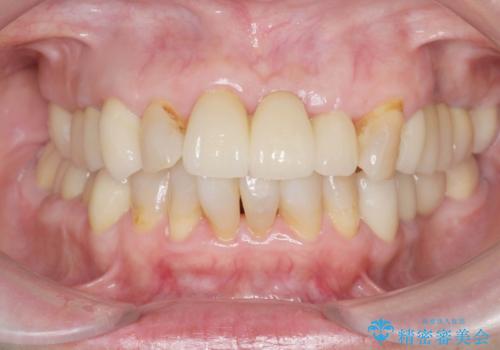

[メタルフリー] 虫歯・銀歯だらけの口腔内を全顎治療

![[メタルフリー] 虫歯・銀歯だらけの口腔内を全顎治療の症例 治療前](https://seimitsushinbi.jp/wp/wp-content/uploads/2025/03/e26a9887bc6905a2f0f51f5772b5ac9c-500x350.jpg?v=1741918285)

![[メタルフリー] 虫歯・銀歯だらけの口腔内を全顎治療の症例 治療後](https://seimitsushinbi.jp/wp/wp-content/uploads/2025/03/530cf6cca6451bc106a9fb69dd58908a-500x350.jpg?v=1741918343)